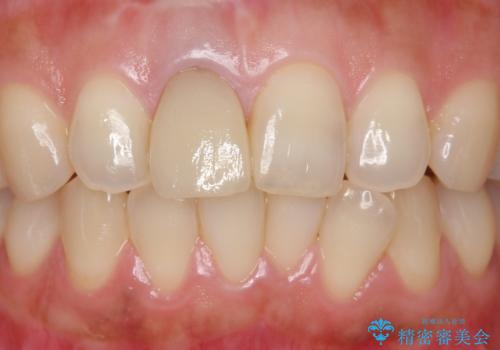

- もっと自然にみえるような差し歯にしたいと希望され来院された患者様です。

患者様の天然歯はグラデーションがあり切縁(歯冠の先端)はやや透けていて透明感があるのに対し、前歯(右上1)の差し歯はやや黄色く不透明で単調な色味でした。

患者様のご希望により、右上1はジルコニアクラウン(スペシャル)、右上5はジルコニアクラウン(スタンダード)へやりかえることにしました。

前歯のクラウンは一度修正し、患者様の理想とする色味や形態を追求しました。

天然歯と見紛うほどの自然な仕上がりに喜んで頂けました。

ジルコニアクラウンの繊細なグラデーション・透明感は熟練した技工士さんの技術の賜物です。

右上1:ジルコニアクラウン スペシャル

右上5:ジルコニアクラウン スタンダード